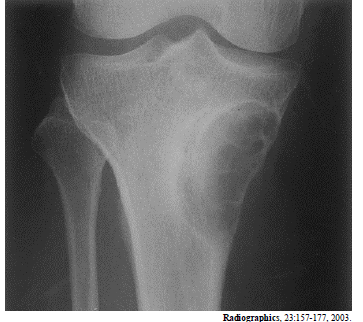

Enunciado 542710-1

A radiografia acima é de um paciente do sexo masculino, com 25 anos de idade, com queixa de dores no joelho. Considerando essa imagem, é correto afirmar que

fibroma não ossificante é um diagnóstico diferencial adequado.

Enunciado 542709-1

a lesão é do tipo metafisária.

Enunciado 542708-1

a lesão tem aspecto de benignidade.

Enunciado 542707-1

a lesão é predominantemente blástica.

Enunciado 542706-1

o diagnóstico mais provável é de tumor de células gigantes.

Enunciado 542705-1

a lesão situa-se na medular.